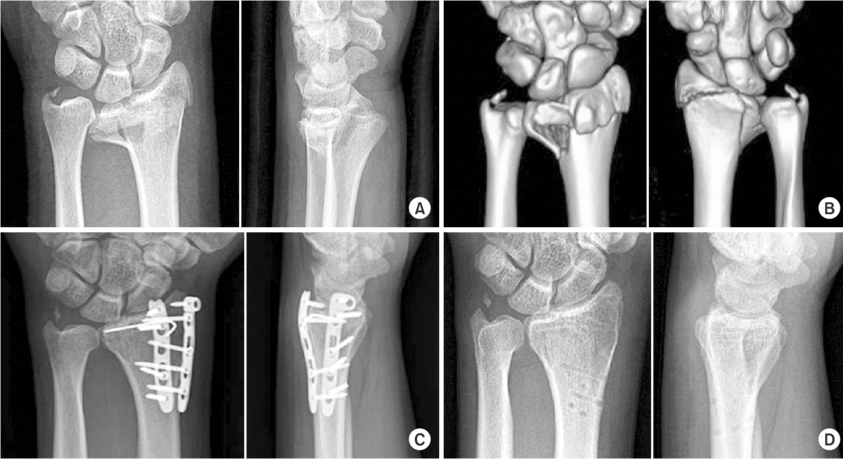

Radiografías: Son la herramienta principal para visualizar las fracturas de muñeca.

Tomografía Computarizada (TC): Puede proporcionar imágenes más detalladas si la radiografía no es concluyente.

Reducción Abierta y Fijación Interna (ORIF): Este procedimiento implica la colocación de placas y tornillos para mantener los huesos en su lugar.